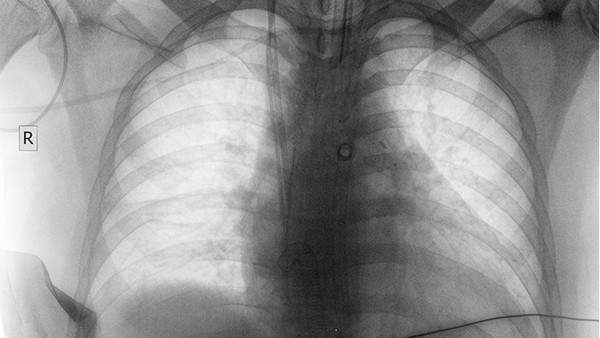

中国医学科学院肿瘤医院是国家癌症中心所在地,在肺癌诊疗方面具有地位。医院拥有的诊断设备,包括PET-CT、MRI等高端影像学检查手段,能够早期发现肺部病变。医院开展肺癌多学科综合治疗,包括手术、放疗、化疗、靶向治疗和免疫治疗等多种治疗方式。医院在微创手术和放疗方面技术,为患者提供个性化治疗方案。医院还参与多项国际多中心临床试验,为晚期肺癌患者提供新治疗机会。

北京大学肿瘤医院在胸部肿瘤诊治方面具有特色优势。医院建立了完善的肺癌诊疗体系,从早期筛查到晚期治疗都有规范化的流程。医院拥有国内的胸腔镜手术技术,能够开展各类复杂的肺癌手术。在放疗方面,医院引进了的放疗设备,能够实施放疗。医院还设有专门的肺癌多学科会诊中心,为疑难病例提供综合诊疗方案。医院注重临床研究,在肺癌靶向治疗和免疫治疗方面积累了丰富经验。

北京协和医院呼吸内科和胸外科在肺癌诊治方面具有悠久历史和丰富经验。医院拥有完善的肺癌诊疗团队,能够为患者提供全方位的医疗服务。在诊断方面,医院开展支气管镜、CT引导下肺穿刺等检查,提高早期诊断率。在治疗方面,医院能够开展各类肺癌手术,包括微创手术和复杂手术。医院还设有专门的肺癌综合治疗中心,整合多种治疗手段,为患者制定佳治疗方案。医院在肺癌基础研究和临床转化方面也取得多项重要成果。

中国人民解放军总医院在肺癌诊治方面具有雄厚实力。医院拥有的医疗设备和专业的医疗团队,能够开展各类肺癌诊疗项目。医院在肺癌早期诊断方面具有优势,采用多种检查手段提高诊断准确率。在治疗方面,医院能够开展各类肺癌手术,包括微创手术和复杂手术。医院还设有专门的肿瘤中心,为肺癌患者提供综合治疗服务。医院注重临床研究,在肺癌治疗新技术应用方面处于地位。

首都医科大学附属北京胸科医院是专门从事胸部疾病诊治的专科医院,在肺癌诊疗方面具有特色优势。医院拥有专业的肺癌诊疗团队和的医疗设备,能够为患者提供全面的医疗服务。医院在肺癌早期诊断方面积累了丰富经验,采用多种检查手段提高诊断准确率。在治疗方面,医院能够开展各类肺癌手术和综合治疗。医院还设有专门的肺癌研究中心,在肺癌诊治新技术研发方面取得多项成果。